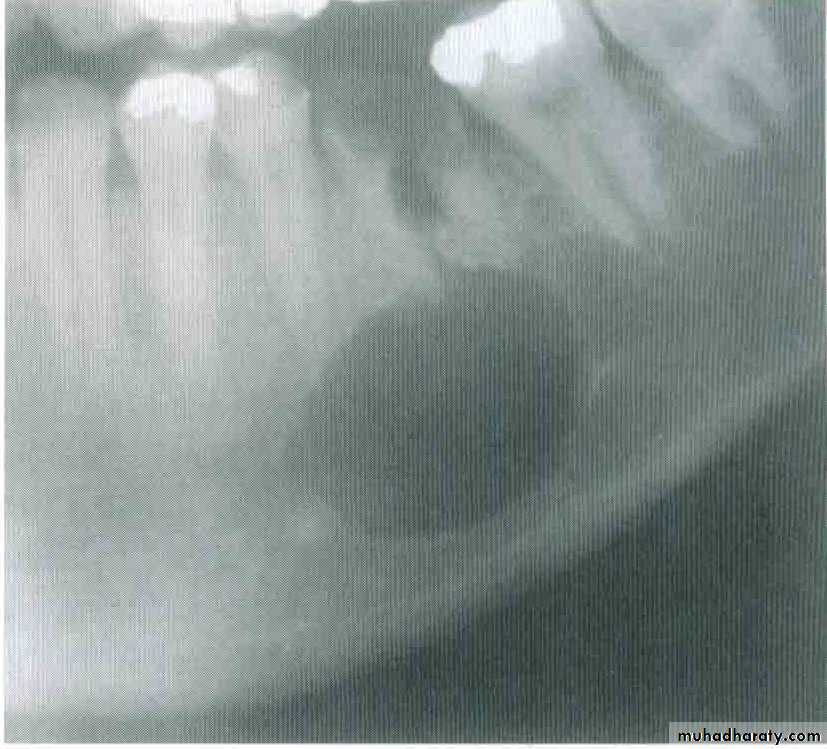

RADIOGRAPHICAL FEATURE

Residual and lateral radicular cyst

A radicular cyst may persist after extraction of the causative tooth.Residual cysts are the most common cause of swelling of the edentulous jaw in older person.